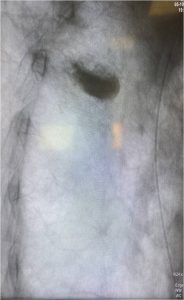

Ι. Μέχρι τις αρχές του 2000, ο έλεγχος στα χειρουργεία όσον αφορά την τοποθέτηση των υλικών σπονδυλοδεσίας και συγκεκριμένα των διαυχενικών βιδών, γινόταν μόνο με λήψη απλών ακτινογραφιών Face και Profil (προσθιοπισθία και πλάγια) με τη χρήση του συστήματος πλοήγησης O-ARM.

α. Η σημαντικότερη συμβολή ήταν η εισαγωγή της διεγχειρητικής δυνατότητας να παρακολουθείται με ακρίβεια η πορεία των τοποθετούμενων διαυχενικών βιδών. Από τα τέλη της δεκαετίας του 2000 άρχισε να γίνεται τοποθέτηση του Συστήματος Πλοήγησης O-ARM στα χειρουργεία.

Το σύστημα αυτό έδινε τη δυνατότητα να παρακολουθείται η θέση και η πορεία των βιδών, οι οποίες έμπαιναν στο πίσω μέρος των σπονδύλων και προωθούνταν περαιτέρω διαμέσου του μίσχου (Pedicle) μέσα στο σπονδυλικό σώμα.

Το σύστημα O-ARM αποτελεί μια εξελιγμένη μορφή Αξονικής Τομογραφίας που δίνει τη δυνατότητα σε πραγματικό χρόνο διεγχειρητικά να ελέγχεται η θέση των υλικών σπονδυλοδεσίας. Αυτή η δυνατότητα παρέχει μεγάλη εμπιστοσύνη στους χειρουργούς της Σπονδυλικής Στήλης για να αποτολμούν πολύπλοκες επεμβάσεις όταν μάλιστα τα ανατομικά όρια των σπονδύλων δεν ήταν σαφή λόγω των παθήσεων, όπως συμβαίνει στις νεοπλασίες και στις κακώσεις ή ήταν σαφώς παραλλαγμένα, όπως συμβαίνει στις συγγενείς ανωμαλίες κατασκευής των σπονδύλων.

Εικόνα 1 (α,β) :Το Σύστημα Πλοήγησης O-ARM

Εικόνα 2 : Οθόνη στην οποία παρακολουθείται από το σύστημα πλοήγησης σε πραγματικό χρόνο η πορεία της διαυχενικής βίδας μέσω του μίσχου (pedicle) εντός του σπονδυλικού σώματος.